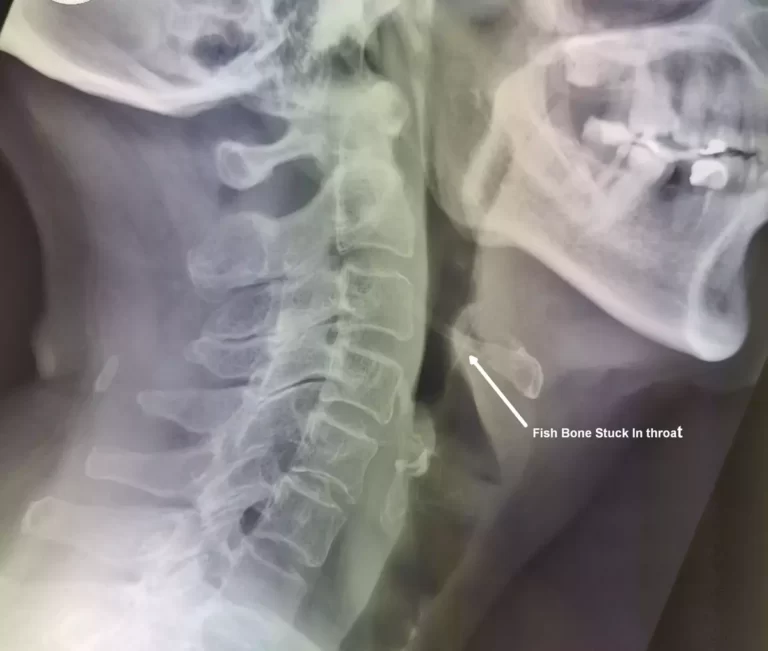

This patient was seen by us in the Accident & Emergency Department. He did not complain of any overt swallowed fish bone symptoms except for mild throat discomfort. An X-ray of the neck showed no fish bone in the throat. Examination of the mouth and the region of the tonsils revealed no fish bone in the throat. However, it is routine to perform flexible nasoendoscopy (putting a small flexible camera) down the nose and deeper down the throat, to rule out any fish bone in the throat further down, or foreign body lodged in the throat. This procedure revealed a fish bone lying horizontally, stuck at the back of the tongue, in front of the voice box. This would not have been seen with a routine examination of the mouth and oral cavity.

- A neck X-ray taken from the side to see if there is a bone in the throat

- A computed tomography (CT Scan)

- A CT scan is a three-dimensional form of imaging which can be more accurate in detection if suspicion is high